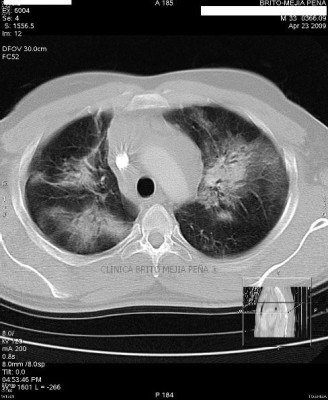

Neumonía